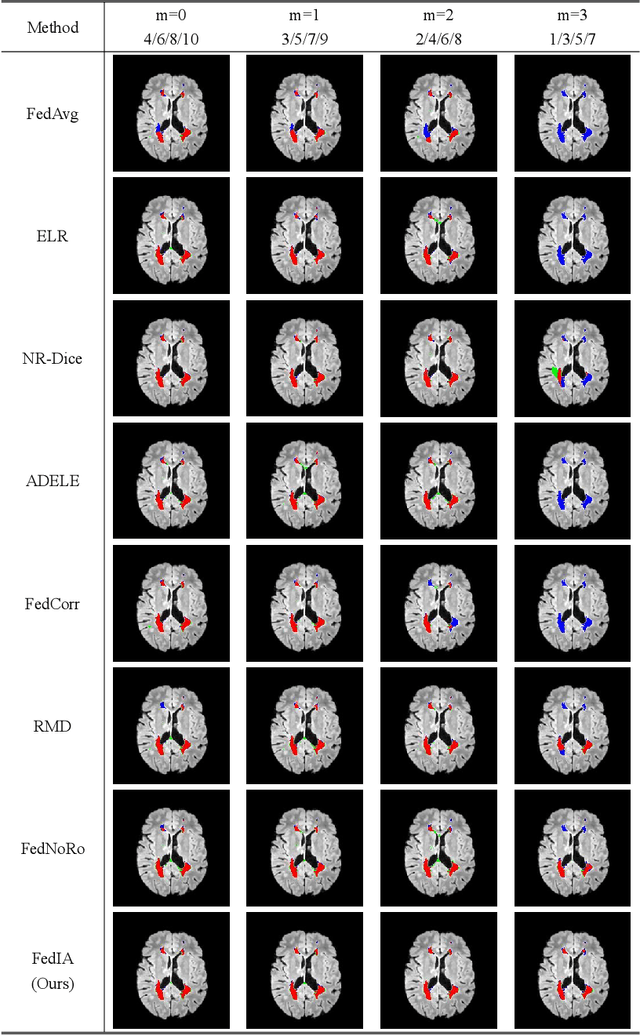

Abstract:Federated learning has emerged as a compelling paradigm for medical image segmentation, particularly in light of increasing privacy concerns. However, most of the existing research relies on relatively stringent assumptions regarding the uniformity and completeness of annotations across clients. Contrary to this, this paper highlights a prevalent challenge in medical practice: incomplete annotations. Such annotations can introduce incorrectly labeled pixels, potentially undermining the performance of neural networks in supervised learning. To tackle this issue, we introduce a novel solution, named FedIA. Our insight is to conceptualize incomplete annotations as noisy data (\textit{i.e.}, low-quality data), with a focus on mitigating their adverse effects. We begin by evaluating the completeness of annotations at the client level using a designed indicator. Subsequently, we enhance the influence of clients with more comprehensive annotations and implement corrections for incomplete ones, thereby ensuring that models are trained on accurate data. Our method's effectiveness is validated through its superior performance on two extensively used medical image segmentation datasets, outperforming existing solutions. The code is available at https://github.com/HUSTxyy/FedIA.